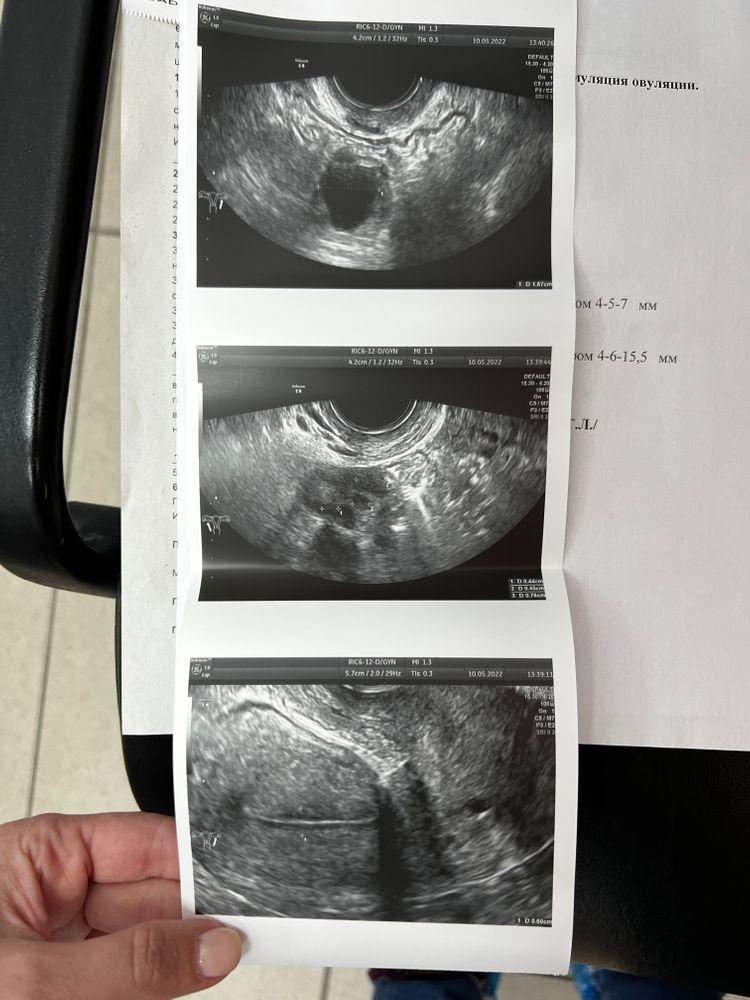

6 день стимуляции, 9 день цикла, узи

10.05.2022

6 день стимуляции, 9 день цикла, узи Всем привет!